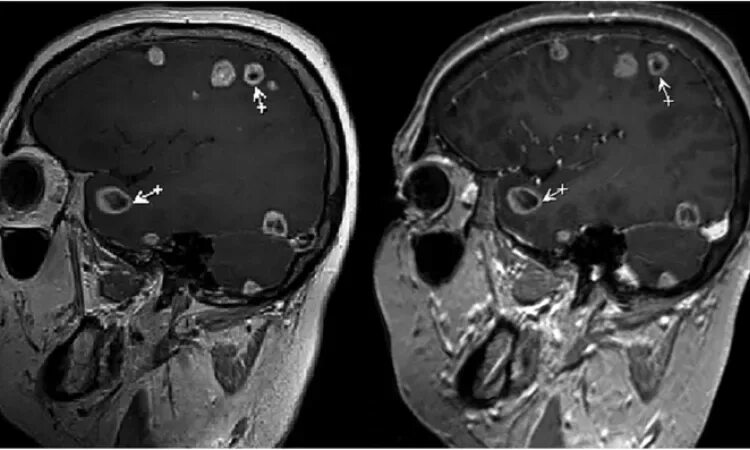

Дают ли метастазы метастазы